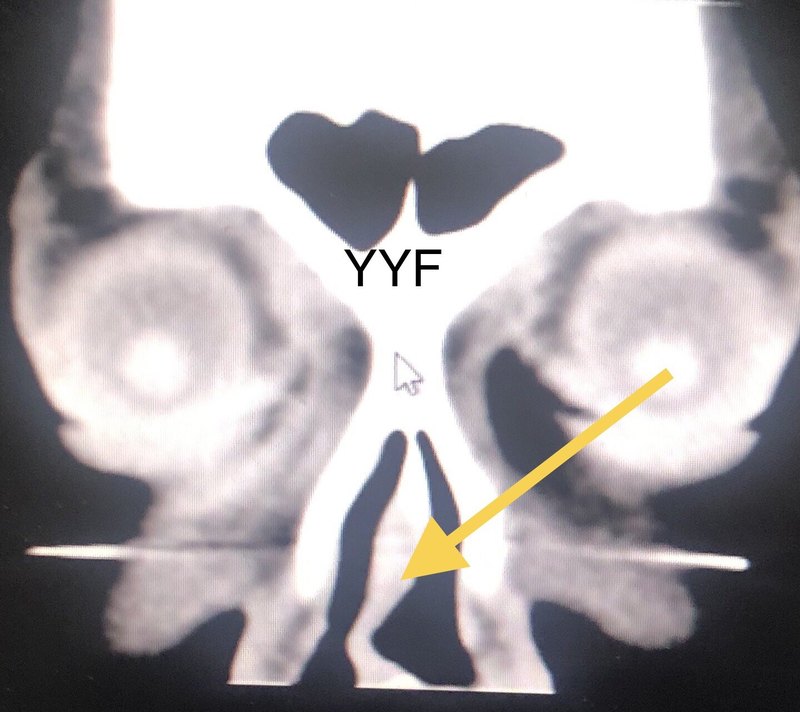

目前95%以上的淚道阻塞患者都是通過鼻內(nèi)鏡下完成淚囊鼻腔吻合術(shù),這一方法已經(jīng)成為鼻淚管阻塞和慢性淚囊炎的首選治療方法。我們?cè)谛g(shù)前的專項(xiàng)評(píng)估中通常完成:1、淚道沖洗明確具體阻塞部位;2、眼眶水平和冠狀位CT明確:A、鼻中隔偏曲是否存在?(比如鼻中隔右側(cè)偏曲就會(huì)影響右側(cè)淚道阻塞的手術(shù)操作,而對(duì)于左側(cè)阻塞不影響,甚至空間大,是好事?。〣、鼻腔空間如何?C、有無鼻腔骨性變異?D、有無患者都不記得的外傷引起的眼眶內(nèi)側(cè)壁骨折?特別是小時(shí)候外傷導(dǎo)致;3、鼻內(nèi)鏡檢查:判斷是否存在鼻腔疾病,影響手術(shù)操作?A、鼻腔息肉?B、鼻腔腫物?(近半年術(shù)前評(píng)估發(fā)現(xiàn)2例鼻腔腫瘤,因?yàn)榱鳒I就醫(yī),最終先活檢明確鼻腔腫物性質(zhì)?。〤、鉤突等鼻腔異常是否存在?鼻內(nèi)鏡和CT檢查各有意義,互相彌補(bǔ),不可或缺,而淚道造影在絕大部分情況下無需進(jìn)行,工作30年,僅做過5次,僅限于嚴(yán)重外傷眼眶骨折后淚道阻塞的淚囊定位和大小判斷!因?yàn)樵煊?、無助于淚道腫瘤性質(zhì)的診斷;2、手術(shù)時(shí)淚囊定位不依靠造影;3、造影時(shí)即使淚囊腔小,成功率相對(duì)低,難道手術(shù)就不做了?我院耳鼻喉科是非常有經(jīng)驗(yàn)的臨床科室,其鼻科優(yōu)勢(shì)不僅是對(duì)于鼻腔、鼻竇疾病的規(guī)范治療,更在于通過鼻內(nèi)鏡下可以完成1、各類復(fù)雜鼻顱底的手術(shù)(有時(shí)耗時(shí)4-15小時(shí))2、垂體瘤手術(shù)3、晚期鼻咽癌的手術(shù)等等我們專業(yè)組和鼻科手術(shù)的聯(lián)合由來已久,合作范圍包括1、眼眶內(nèi)側(cè)深部腫瘤2、甲狀腺眼病,鼻內(nèi)鏡下內(nèi)壁深部減壓3、淚囊腫瘤的聯(lián)合切除手術(shù)4、視神經(jīng)管減壓5、鼻眶溝通腫瘤6、額竇疾病的手術(shù)等等今后陸續(xù)演示!本例患者中年女性,術(shù)前評(píng)估時(shí)發(fā)現(xiàn)鼻中隔S形彎曲,鼻腔前端操作空間極其有限,(需要注意的是,鼻中隔偏曲形態(tài)和程度各異,而鼻部外觀幾乎都完全正常)鼻中隔矯正手術(shù)耗時(shí)30分鐘;淚道吻合手術(shù)我目前操作的時(shí)間平均30分鐘;1、術(shù)后患者鼻腔通氣明顯改善;2、手術(shù)吻合口良好,淚道通暢;3、鼻腔空間增大有利于術(shù)后復(fù)查;4、鼻腔空間改善,可以避免吻合口等部位和鼻中隔的異常粘連聯(lián)合手術(shù)確保存在鼻腔異常的情況下,我們依舊可以在鼻內(nèi)鏡下完成淚道手術(shù),而無需采用皮膚面切口。當(dāng)然對(duì)于高齡患者,從來不存在鼻腔通氣異常的淚道阻塞,也可以選擇經(jīng)皮膚面完成淚道吻合手術(shù),而無需進(jìn)行鼻中隔矯正!否則:1、手術(shù)操作翻倍,增加術(shù)后出血概率;2、術(shù)后雙側(cè)鼻腔填塞防止出血,因?yàn)橥獠粫?,?duì)于老年患者容易誘發(fā)其他內(nèi)科疾病;3、有外路手術(shù)可以替代因?yàn)槠つw面入路對(duì)于鼻腔操作空間要求并不高,而術(shù)后皮膚絕大多數(shù)也沒有明顯的疤痕!尤其是年長者的皮膚皺紋可以遮掩傷口。